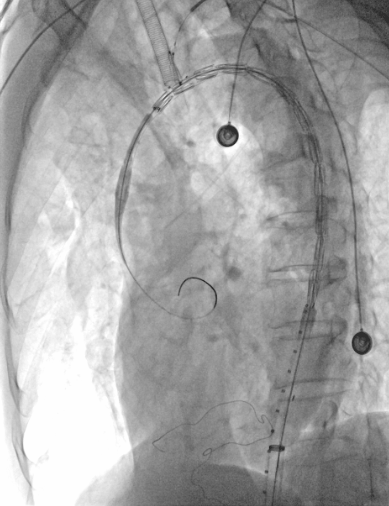

2、从右侧股动脉沿超硬导丝上推输送系统至降主动脉,褪下支架软鞘后,上推支架,助手配合牵拉分支导丝,使分支支架进入LSA;

动脉长鞘怎么置入【弓部重建直通车】真腔难觅,另辟蹊径|潍坊市人民医院血管外科运用Castor®支架结合长鞘建立导丝通路治疗主动脉夹层两例_https://www.jmylbn.com_新闻资讯_第10张

上推支架

3、再次造影确认后,释放支架;

4、术后造影显示,主动脉夹层第一破口被有效隔绝,LSA血流通畅,真腔得到重塑,支架无移位或内漏现象发生,手术圆满成功。

动脉长鞘怎么置入【弓部重建直通车】真腔难觅,另辟蹊径|潍坊市人民医院血管外科运用Castor®支架结合长鞘建立导丝通路治疗主动脉夹层两例_https://www.jmylbn.com_新闻资讯_第11张

术后造影